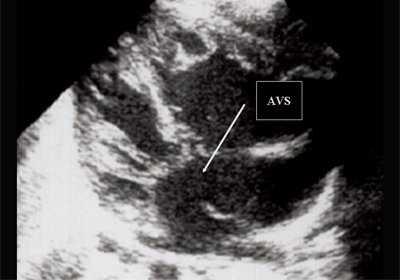

Антенатально при равных величинах давления в желудочках сердца и в предсердиях объемной перегрузки не возникает. В связи с этим ни один из эхокардиографических гемодинамических признаков, используемых у детей и взрослых, не выявляется у плода. К эхокардиографическим проявлениям порока антенатально относится только прямой признак - перерыв ультразвукового луча в области дефекта. Размеры сердца, соотношение размеров желудочков сердца не отличаются от нормы (рис. 5).

Рис. 5. Четырехкамерное сечение сердца плода. Стрелкой указан первичный дефект межпредсердной перегородки (АVS).